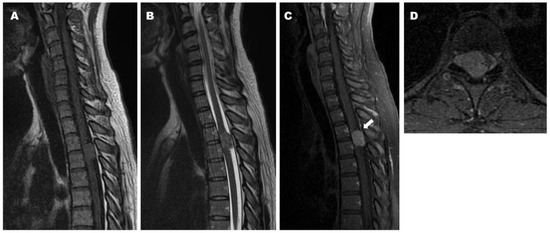

2.1. Case 1

2.2. Case 2